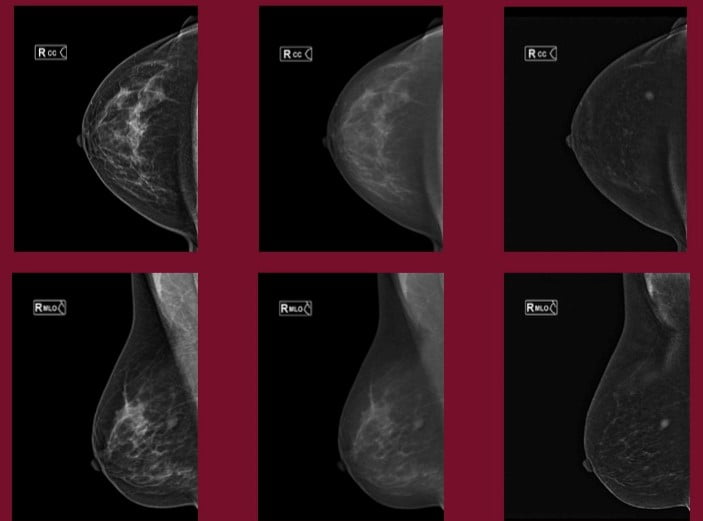

Il limite della Mammografia è rappresentato dalla “mammella densa”, nella quale strutturalmente prevale la quota di tessuto ghiandolare rispetto a quello adiposo; condizione genetica a ogni età e presente soprattutto nelle donne giovani, in età fertile.

La radiopacità omogenea indotta dal tessuto ghiandolare, fa sì che ci sia la possibilità che la lesione non sia individuata.

La ricerca tecnologica ha perciò cercato di sopperire a tali limiti della mammografia digitale sviluppando la MAMMOGRAFIA CON TOMOSINTESI.

La TOMOSINTESI è una procedura diagnostica che permette di studiare la mammella ‘a strati’, come la TC; la mammella viene scomposta in tante immagini che poi, sovrapposte, ricostruiscono la figura della mammella nella sua completezza.